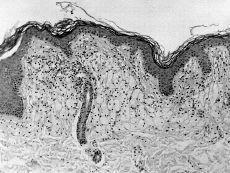

Se realizó biopsia de lesiones cutáneas observándose a nivel de la dermis acúmulo de células espumosas sin células gigantes tipo Touton y con algunos linfocitos perianexiales (Fig. 2).

FIG.2.--Infiltrado en dermis de células espumosas con linfocitos perianexiales.

Histológicamente se caracteriza por un infiltrado en dermis de células espumosas, siendo rara la presencia de infiltrado linfocitario y células gigantes tipo Touton (3, 4, 10, 12-14). Menos frecuente es observar áreas de necrobiosis focal y progresión a xantogranuloma necrobiótico, sugiriendo algunos autores que el xantoma plano difuso normolipémico y el xantogranuloma necrobiótico (entidad con la que hay que hacer dignóstico diferencial) pudieran representar parte del espectro de reacciones dérmicas xantomatosas asociada a paraproteinemia (4, 15).